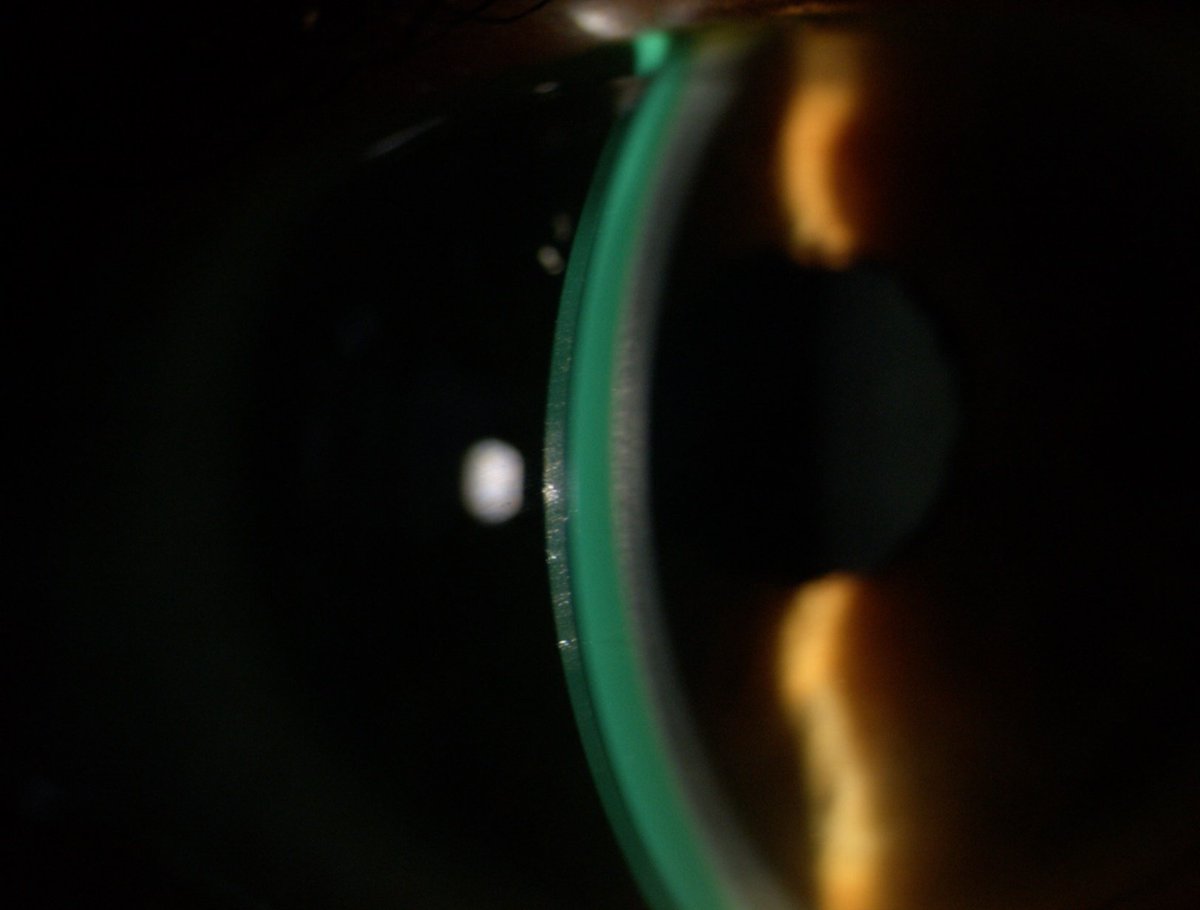

Last week our final year students @PlymOptometry had hands-on experience in fitting and assessing mini-scleral contact lens. Thanks to Ian Sexton from @CooperVisionUK in helping to run this workshop. #miniscleral #specialitycontactlens

mrj_vision's tweet image. Last week our final year students @PlymOptometry had hands-on experience in fitting and assessing mini-scleral contact lens. Thanks to Ian Sexton from @CooperVisionUK in helping to run this workshop. #miniscleral #specialitycontactlens

This week we had a session on mini-scleral lenses from @MeniconUK for our final year @PlymOptometry students. It was great to see their enthusiasm and skill to fit and assess the lenses. Thanks to Josie, James and Hans from @Meniconuk for running these sessions.

mrj_vision's tweet image. This week we had a session on mini-scleral lenses from @MeniconUK for our final year @PlymOptometry students. It was great to see their enthusiasm and skill to fit and assess the lenses.

Thanks to Josie, James and Hans from @Meniconuk for running these sessions.